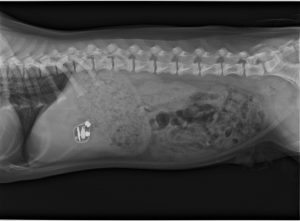

今日は5.5ヵ月の中型犬の男の子、育ち盛りやんちゃ盛りです。食べてしまったのはコードレス・イヤフォンの片方。レントゲンにもはっきり写っています。これはもう吐かせるしかありません、吐剤を注射してすっきり吐いてくれました。その後も元気食欲一杯で、吐いたばかりの吐物をまたすぐ食べようとしてあわてて取り除いたくらい。う~ん、可愛い盛りだけれど飼主さんは大変ですね。